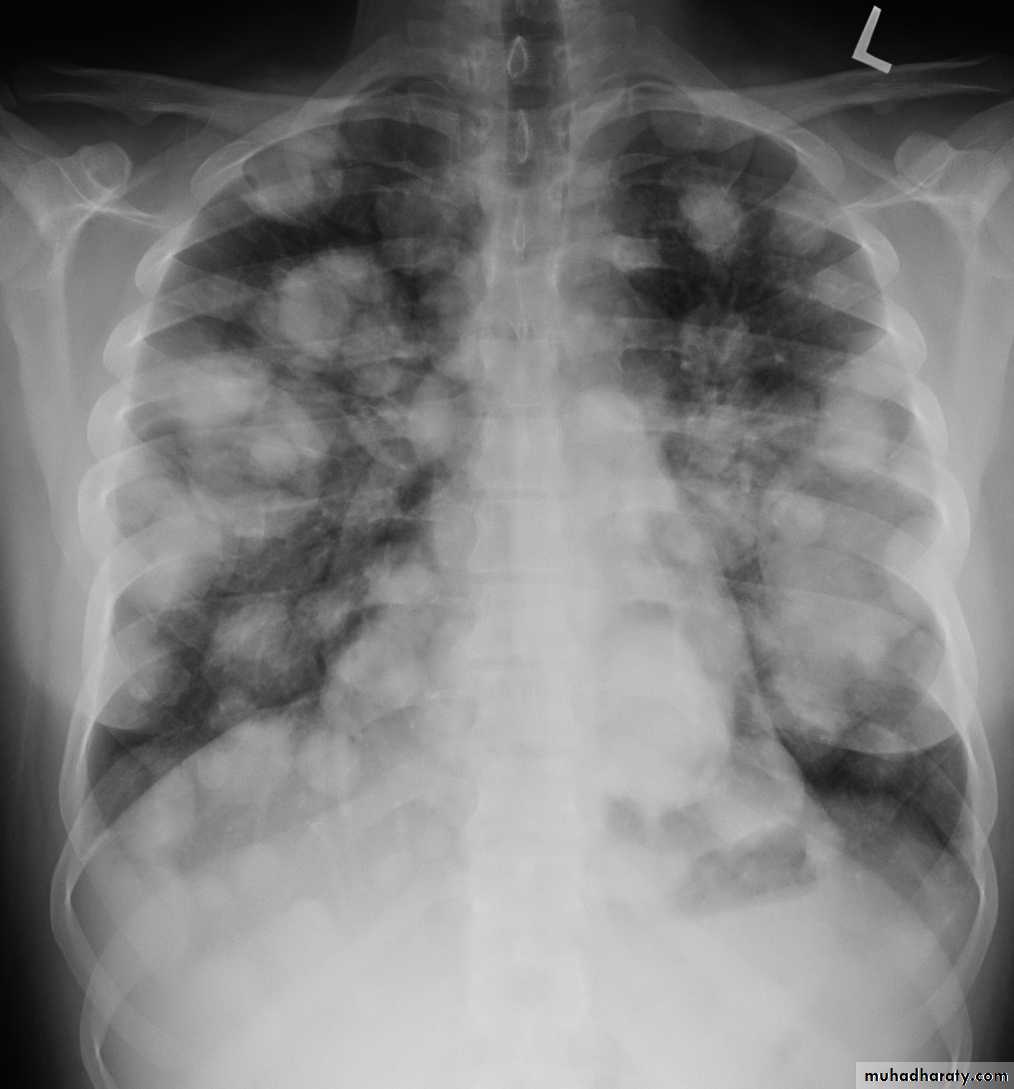

Pulmonary metastases are common and the result of metastatic spread to the lungs from a variety of tumors and can spread via blood or lymphatics.1.Cannonball metastases refer to large well circumscribed, round multiple opacities like cannonballs